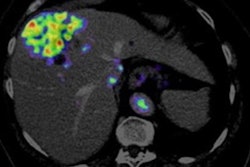

- Malignant bone disease (2.4%)

Indeterminate lesion on PET/CT classified by PET/MRI for 53-year-old man with lung cancer. Contrast-enhanced CT (A), PET (B), and fused F-18 FDG PET/CT (C) images are displayed in comparison with contrast-enhanced T1-weighted MRI (D), PET (E), and fused F-18 FDG PET/MRI (F) images. In CT (A), hyperdense, subcentimeter liver lesion (arrows) in segment VII is suggestive of transient hepatic attenuation difference or small hemangioma. As malignancy cannot be excluded, it needs further investigation. On PET/MRI, lesion is clearly classified as metastasis because of contrast enhancement and tracer uptake due to later acquisition time point. Follow-up CT confirmed diagnosis after 78 days. Image courtesy of the Journal of Nuclear Medicine.After exclusions, the researchers examined 1,003 PET/MRI scans of 918 patients. PET/MRI outperformed PET/CT in terms of providing more tumor information (26.3%), mostly in patients with malignant bone disease, followed by lung cancer, prostate cancer, and gynecologic or breast cancer. PET/MRI identified additional malignant findings in 5.3% of cases, which lead to a change in tumor, node, and metastases (TNM) staging in 2.9% of cases. PET/MRI also clearly classified indeterminate PET/CT lesions in 11% of cases.